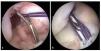

Fig. 11 La guía se extrae y se controla la posición del agujero remanente insertando el artroscopio dentro de la articulación a través del portal medial. Línea negra: línea intercondílea; línea punteada negra: interfaz huesocartílago; línea punteada roja: zona de inserción. AM: inserción del haz AM; PL: inserción del haz PL.

Fig. 15 a) La imagen muestra la posición del túnel femoral en el centro de la inserción femoral. b) A través del portal medial se controla la posición del túnel femoral. Línea punteada negra: interfaz hueso-cartílago; línea punteada blanca: línea intercondílea; línea punteada roja: inserción del LCA; línea punteada azul: interfaz hueso-cartílago. AM: inserción del haz AM; PL: inserción del haz PL.